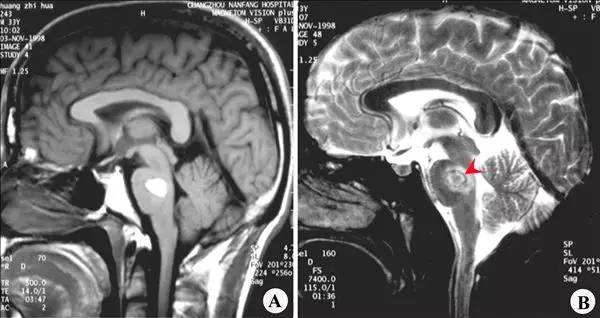

医生一看问的比较专业,因为人脑分为大脑、小脑和脑干;脑干又是由三个部分组成,中脑、脑桥和延髓。

1、脑是人最重要的器官,而脑干又是人脑中最重要的部位,管人的呼吸和心跳的地方就在这里,还有链接大脑与身体的重要传导通路。

2、脑干重要但占得地方却很小,大约自己大拇指这么粗,并且对外界影响反应剧烈,以前这里是脑科手术的禁区,现在很多水平高超的神经外科医生已经可以做脑干部位手术了。在手术过程中滴上一滴水病人呼吸和心跳都会有明显的变化。

4、脑干并不是一个部位,它包括中脑,脑桥,延髓三部分,不同部位出血症状是不一样的,但这些地方都很重要,一般如果出血5毫升以上就算出血量大的,预后相对较差。